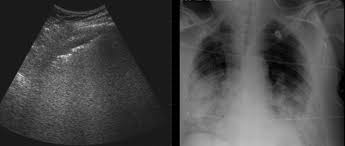

Ultrasound Chest

An Ultrasound Chest is a non-invasive test that uses sound waves to create images of the organs in your chest, including the lungs and heart. This scan helps identify conditions like fluid in the lungs, tumors, or infections, providing detailed images that allow doctors to make accurate diagnoses. The chest ultrasound is particularly useful for patients experiencing symptoms such as chest pain, difficulty breathing, or persistent cough. This test is quick, painless, and safe, making it an effective tool for monitoring various chest-related health issues.